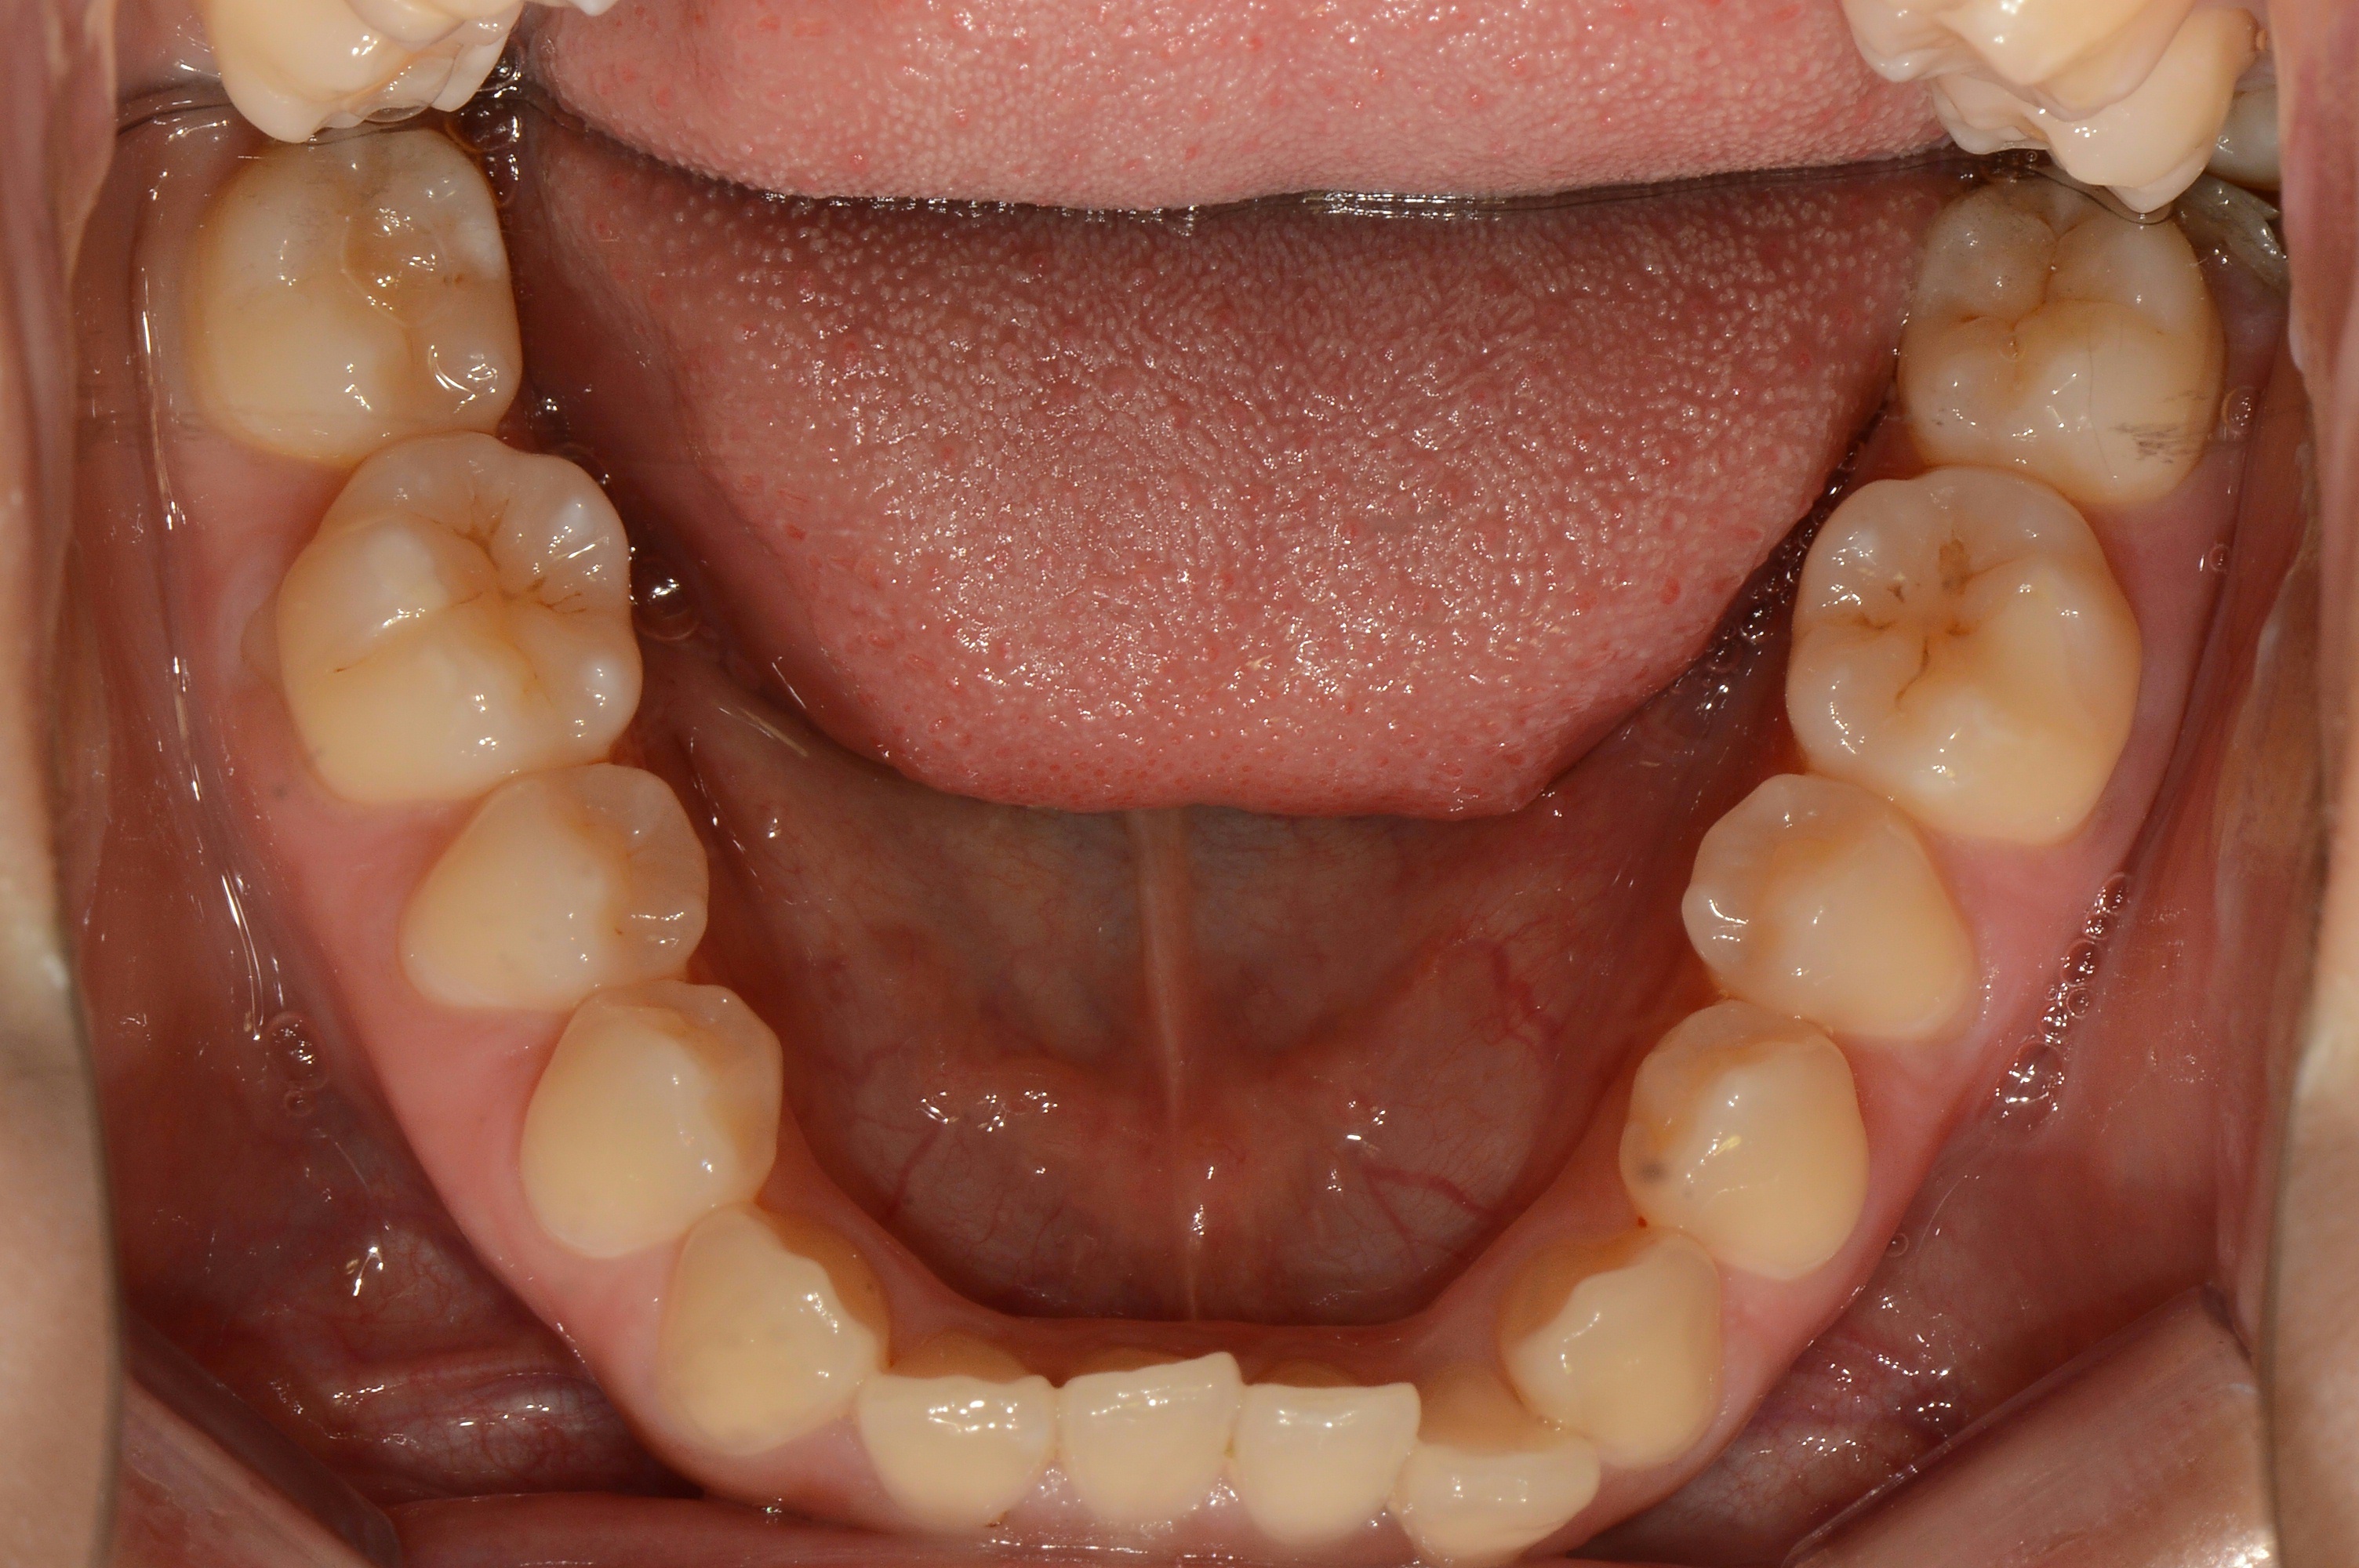

치료 전 사진입니다.